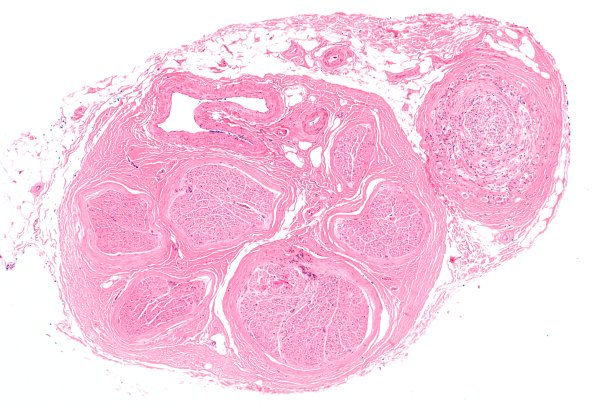

Washington University Experience | PERIPHERAL NEUROPATHY | 19 TRAUMATIC INJURIES | 10A1 Neuroma (Case 10) H&E 4X

Case 10 No History ---- The patient is an 83 year old woman with no history provided in this old case. Operative procedure: Biopsy ---- 10A1,2 Microscopic examination of the sural nerve biopsy shows multiple fascicles, only one of which shows concentric axonal sprouting, a myxoid background and formation of mini-fascicles. (H&E)